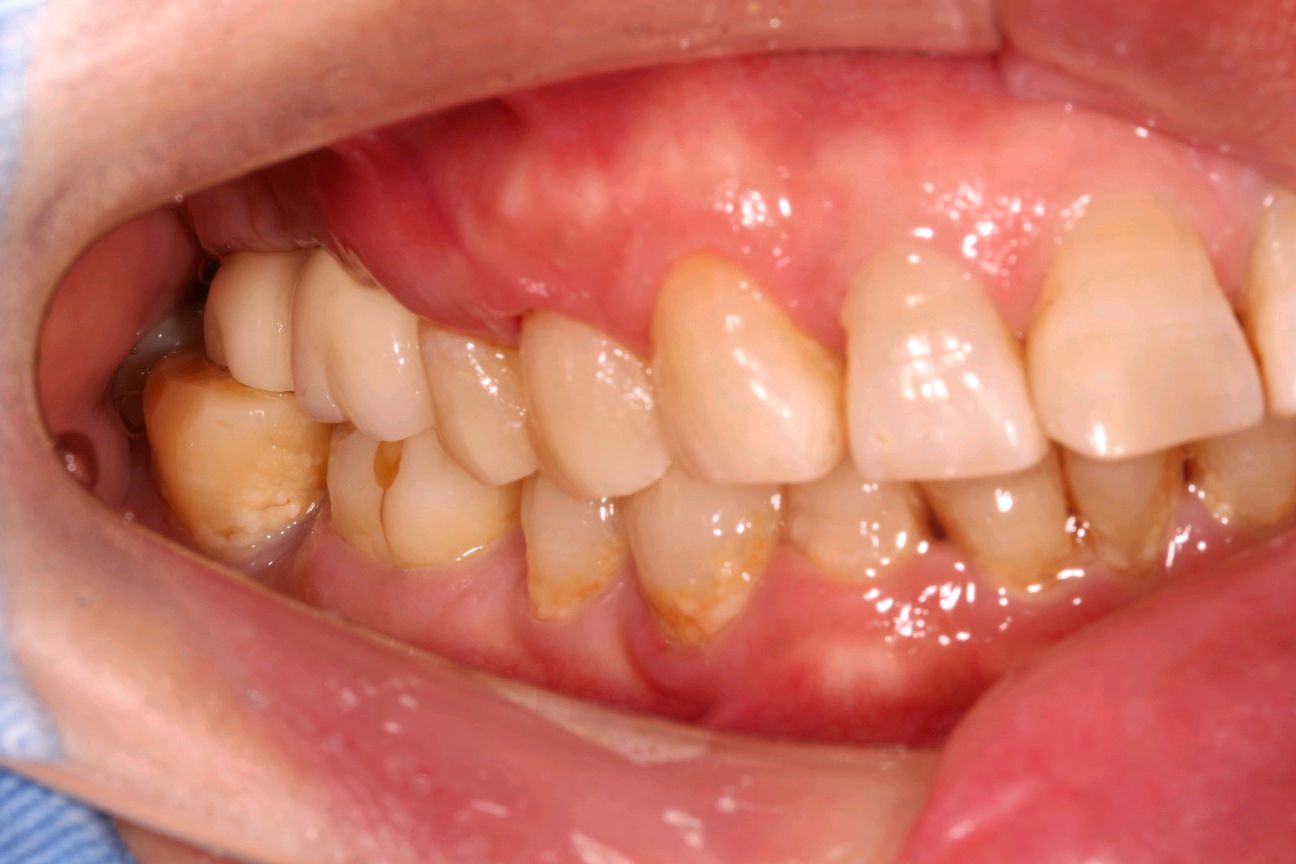

患者女,65 岁。右上 6、7 已做过两颗种植牙,因右上 5 松动,影响咀嚼,要求治疗。 口腔检查:右上 67 种植牙存,右上 5 叩诊+,探诊深牙周袋,冷热无反应,龈周-。X 线示 根尖周大面积阴影,颌面可见近远中折裂。诊断慢性根尖炎,牙根折裂。无法保留,建议拔除后,种植修复。

术前